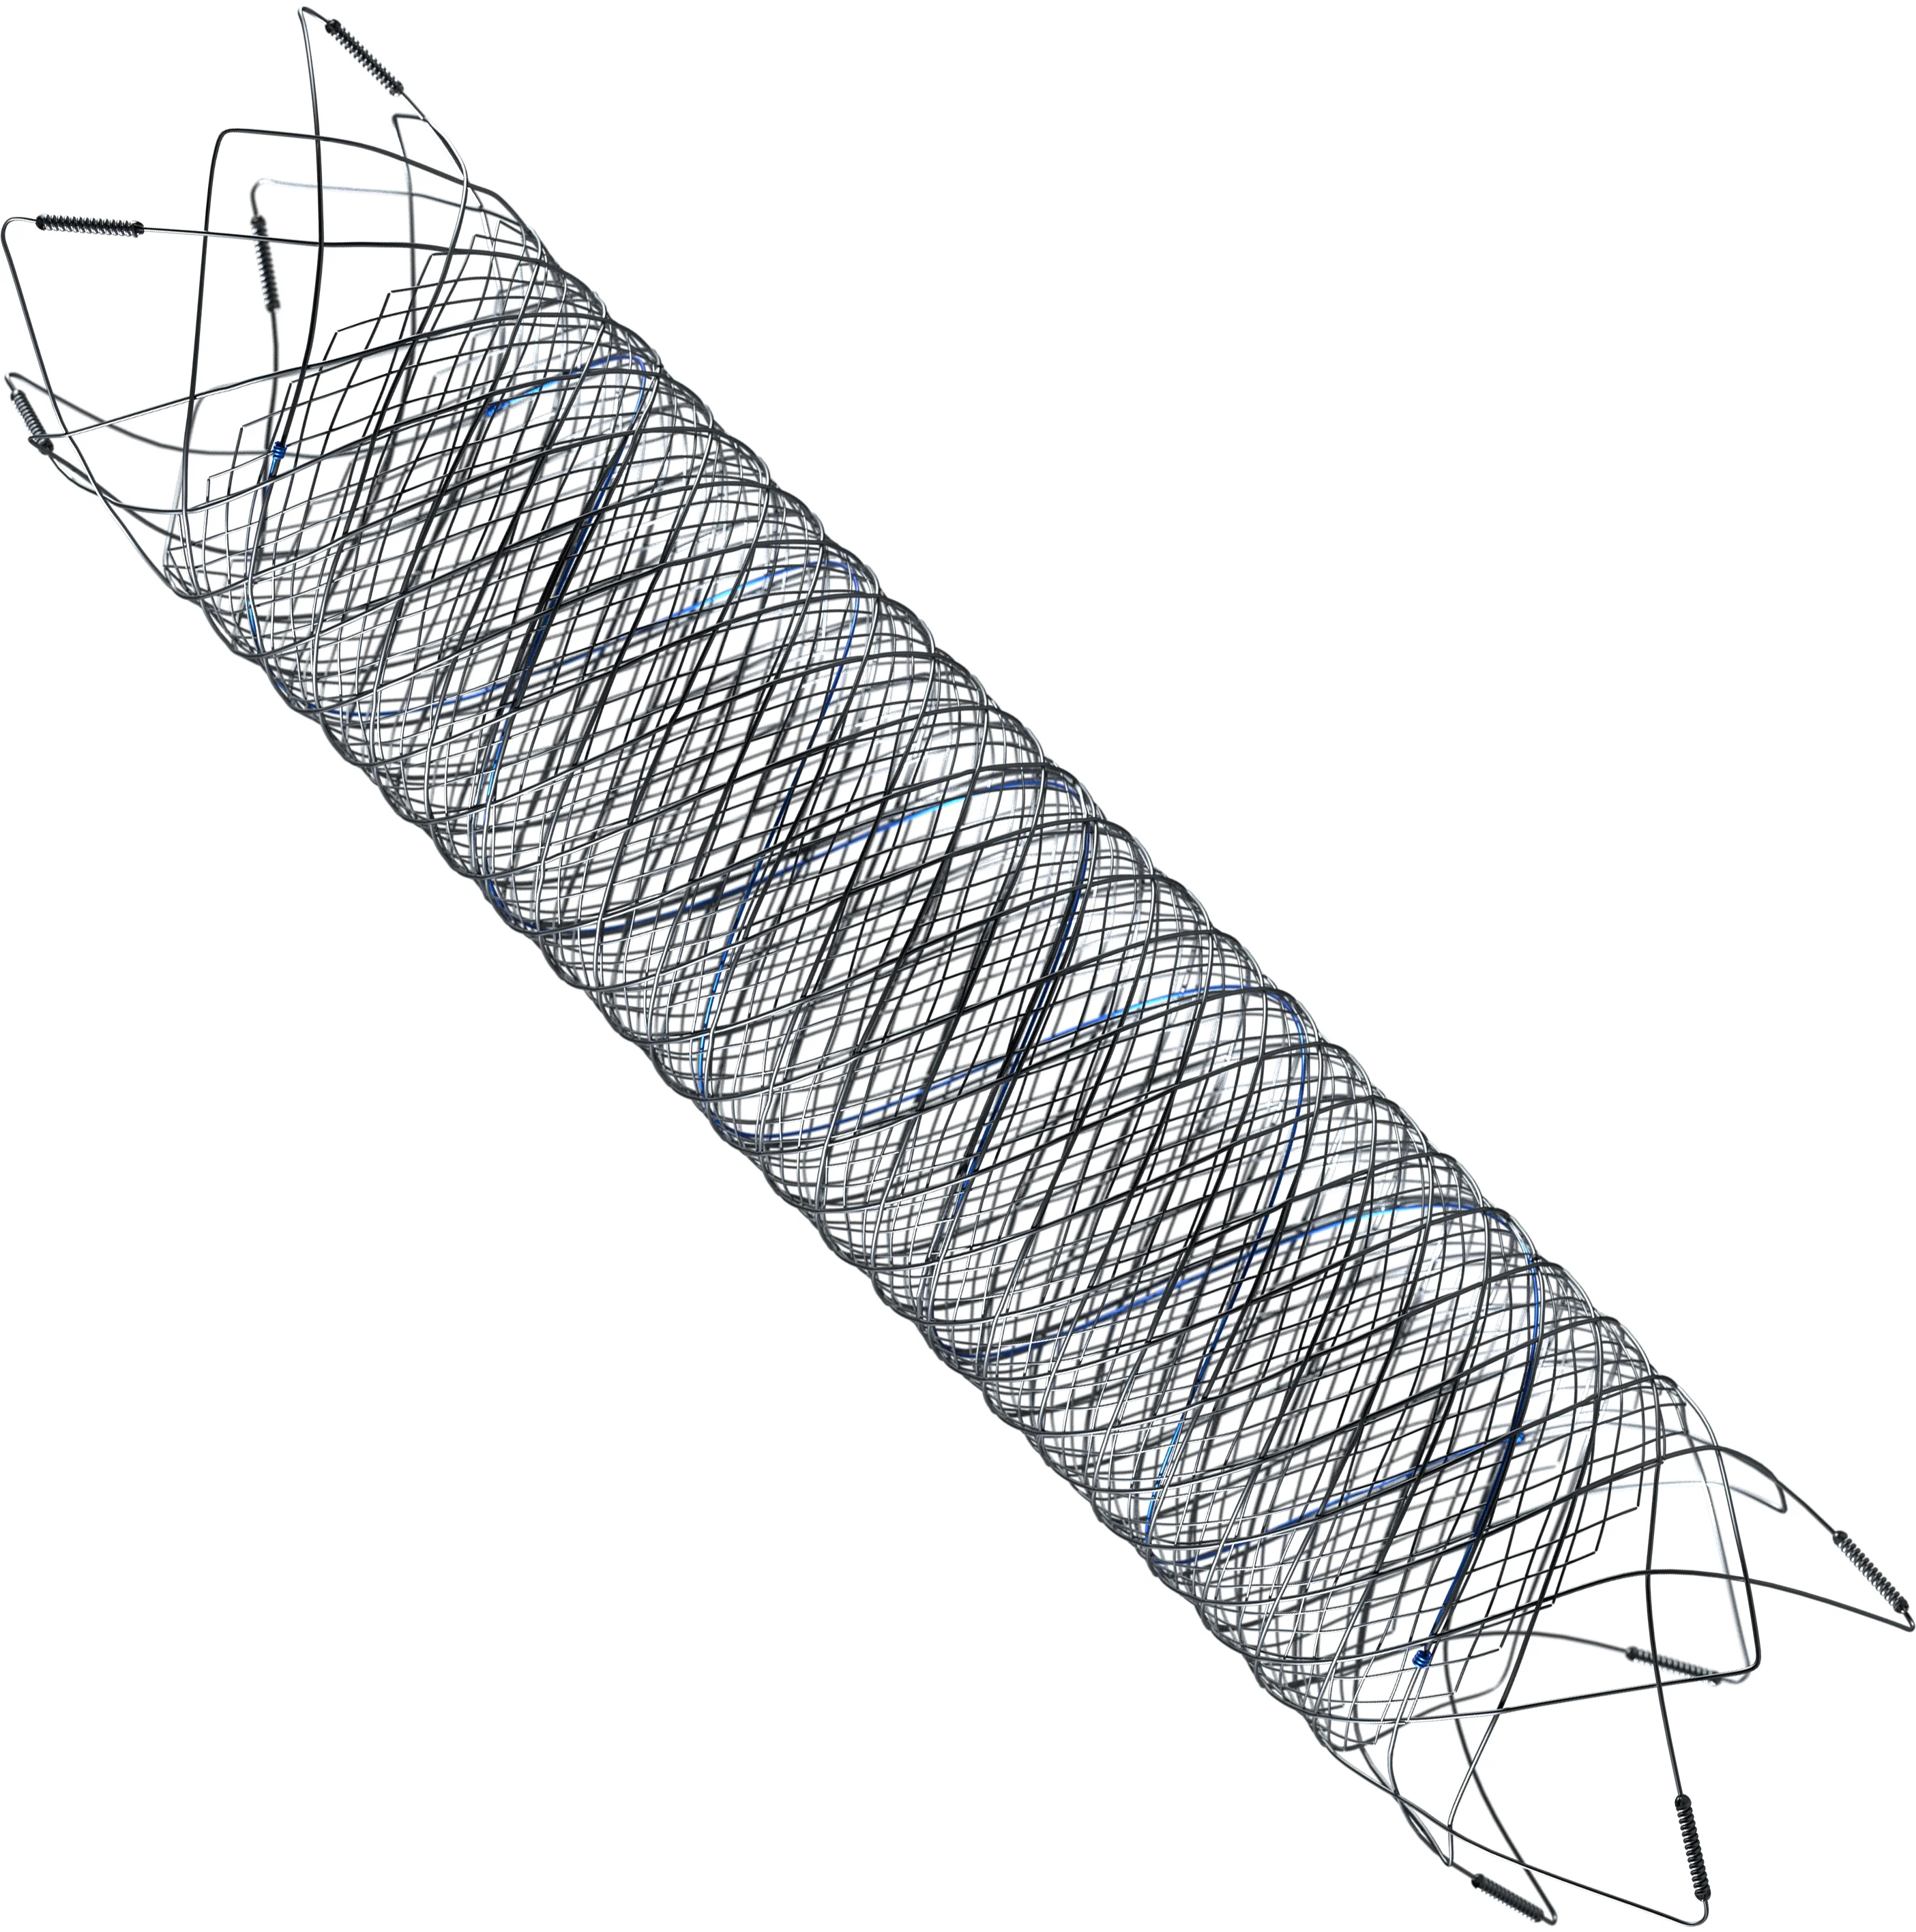

03 — Flow Diversion

The Flow Diversion technique uses a low porosity stent across a wide-necked brain aneurysm. The device is placed across the aneurysm neck opening, and extends into the parent artery on both sides. This alters intra-aneurysmal blood flow patterns and redirects flow away from the aneurysm

FRED™

Flow Diverter

FRED™ X

The Next Advancement in Flow Diversion Technology